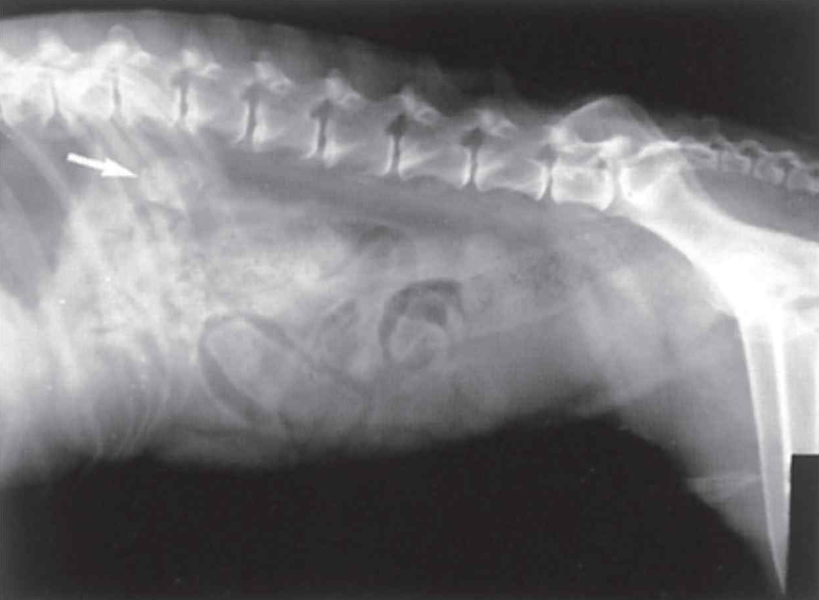

| Radiography (Abd.) - Excellent abdominal detail - Hepatomegaly - Distention of urinary bladder - Cystic calculi - Adrenal mass - Calcified adrenal gland - Dystrophic calcification of soft tissues, calcinosis cutis - Osteoporosis of vertebrae | ![]() |